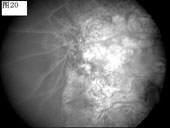

优秀眼底图片奖应征作品展示

17 18 19 20